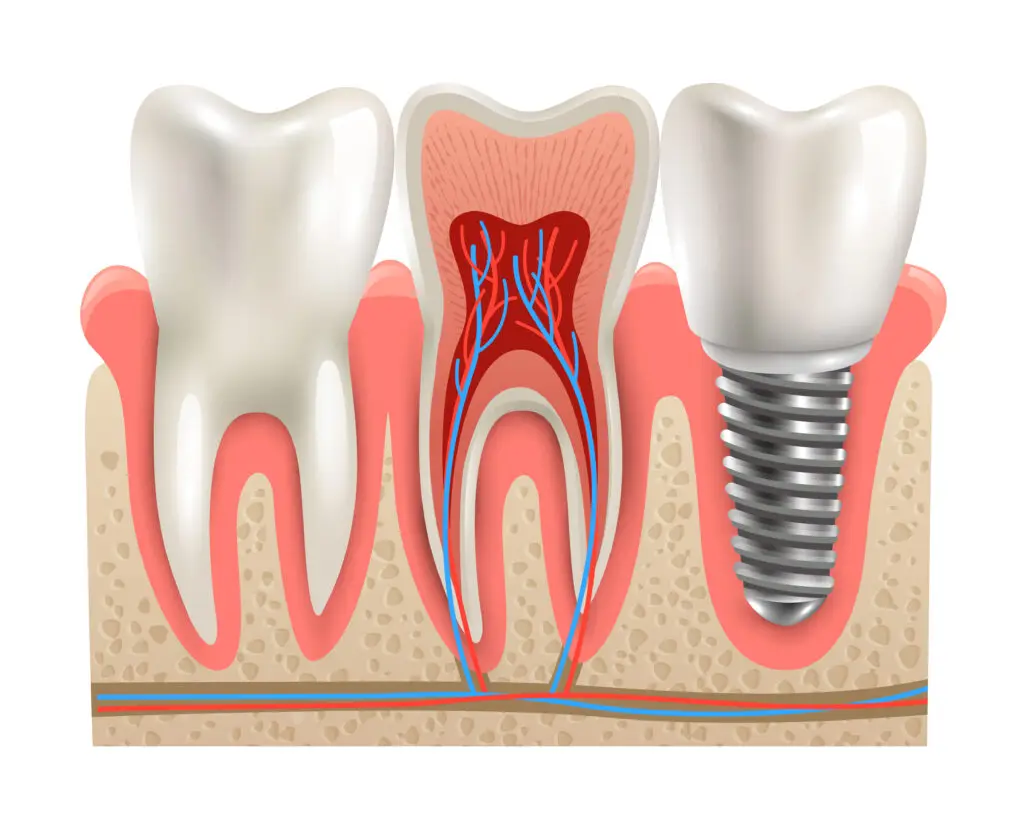

A root canal is performed when the pulp—the soft tissue containing nerves and blood vessels inside the tooth—becomes infected or inflamed. Instead of extracting the tooth, the dentist removes this damaged tissue, fills the empty canals with a biocompatible, rubbery material (gutta-percha), and restores the tooth to full function.